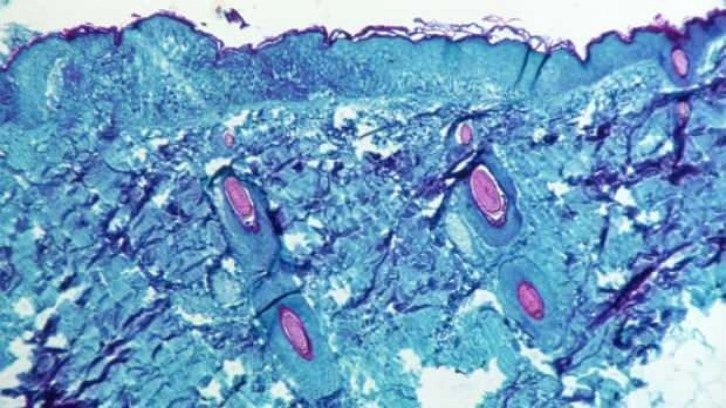

Endemik bir virüsün neden olduğu nadir hastalıklardan biri olarak bilinen maymun çiçeği, Kongo ve Batı Afrika türü olmak üzere ikiye ayrılıyor.

Genellikle hayvandan insana ve nadiren insandan insana yakın temasla bulaşan virüs, vücutta yüksek ateş ve kaşıntılı kabarcıklara yol açabiliyor.